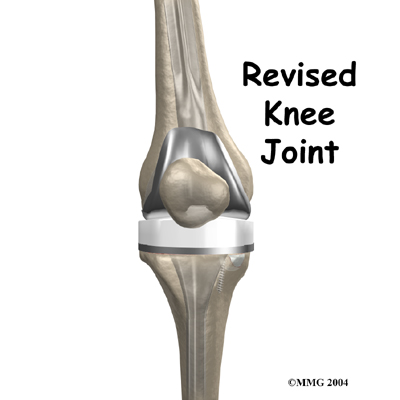

Over the past 30 years, artificial knee replacement surgery has become increasingly common. Millions of people have gotten a new knee joint. The first time a joint is replaced with an artificial joint the operation is called a primary joint replacement. As people live longer and more people receive artificial joints, some of those joints begin to wear out and fail. When an artificial knee joint fails, a second operation is required to replace the failing joint. This procedure is called a revision arthroplasty.

Before describing the revision procedure, let's look at the revision prosthesis itself.

The Revision Prosthesis

There are two major types of revision implants:

- cemented prosthesis

- uncemented prosthesis

A is held in place by a type of epoxy cement that attaches the metal to the bone. An has a fine mesh of holes on the surface that allows bone to grow into the mesh and attach the prosthesis to the bone.

Both are still widely used. In many cases a combination of the two types is used. The patellar (kneecap) portion of the prosthesis is commonly cemented into place. The decision to use a cemented or uncemented artificial knee is usually made by the surgeon based on your age, your lifestyle, and the surgeon's experience.

Each prosthesis is made up of three main parts.

The tibial component (bottom portion) replaces the top surface of the lower bone, the tibia. The stem of the tibial component used in revision surgery is usually much longer than the type used for primary knee replacements. This is because the bone of the tibia is usually not the same as when the initial replacement was done. The bone may be weaker, or there may be areas inside the tibia where bone is missing. A longer stem can reach further down the tibial canal and distribute your body weight better. It also gives the body a greater surface area for healing, which can improve fixation of the implant to the bone inside the tibia.

The femoral component (top portion) replaces the bottom surface of the upper bone (the femur) and the groove where the patella fits. Like the tibial component used in revision, the femoral component often has a long stem.

The patellar component (kneecap portion) replaces the surface of the patella where it glides in the groove on the femur.

The tibial component is usually made of two parts: a metal tray that is attached directly to the bone, and a plastic spacer that provides the slick surface. The femoral component is made of metal. In some types of knee implants, the patellar component is made of a combination of metal and plastic.